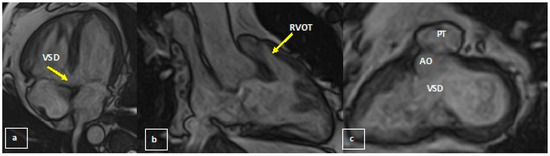

The Case of a 44-Year-Old Survivor of Unrepaired Tetralogy of Fallot, Right Aortic Arch and Abdominal Aortopulmonary Collateral Vessels

2. Case Report

2.1. Initial Work Up

2.2. Diagnosis and Management